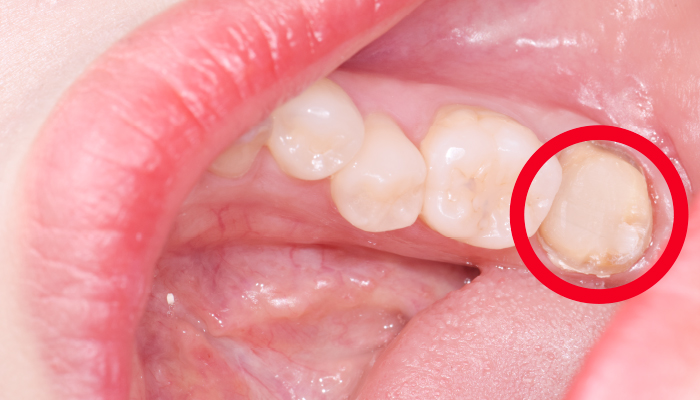

이갈이는 다양한 원인에 의해 발생되는 것으로 치아의 마모, 턱관절 통증, 두통 등을 유발합니다. 치과치료와 함께 생활습관을 교정하는 방법으로 이갈이를 줄여나갈 수 있습니다.

다양한 합병증을 동반하는 이갈이